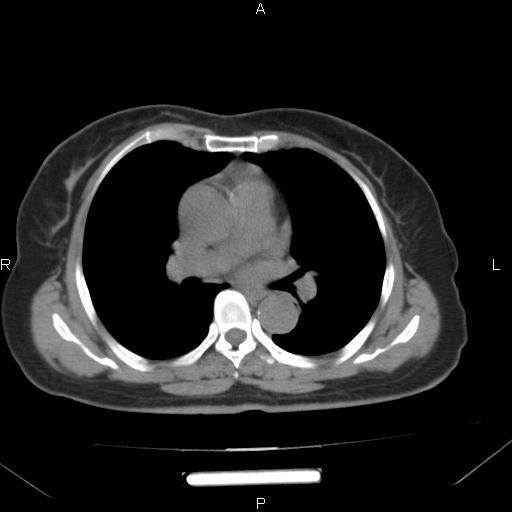

胸腺瘤

女、63Y 双眼睑下垂,早轻晚重。 胸腺瘤???

结果胸腺瘤